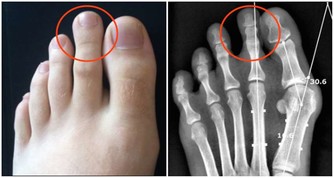

是否便祕? 視糞便硬度關於便秘,比起次數,糞便的硬度更為重要。美兆健康管理機構研發處研發長劉婷婷博士表示,倘若糞便很硬且成粒狀,即使是每天都有排便,其實也屬於便秘一族。因為過硬的糞便在通過腸道與肛門等部位時,容易造成物理性的損傷,引起發炎,糞便中的毒素也會持續地回收,導致慢性病的發生。而糞便的硬度是由大腸內容物的體積與含水量來決定。特別是體積對於糞便是不是能夠軟硬適中,有決定性的影響。